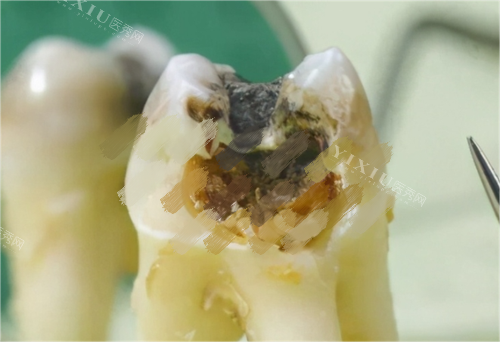

医院按常见项目划分为“种植牙”“牙齿矫正”“牙齿修复”三大核心科室。种植牙科针对单颗/多颗缺牙、全口缺牙;矫正科涵盖儿童早期干预、青少年及成人传统托槽/隐形矫正;修复科则处理补牙、牙冠、贴面等问题。